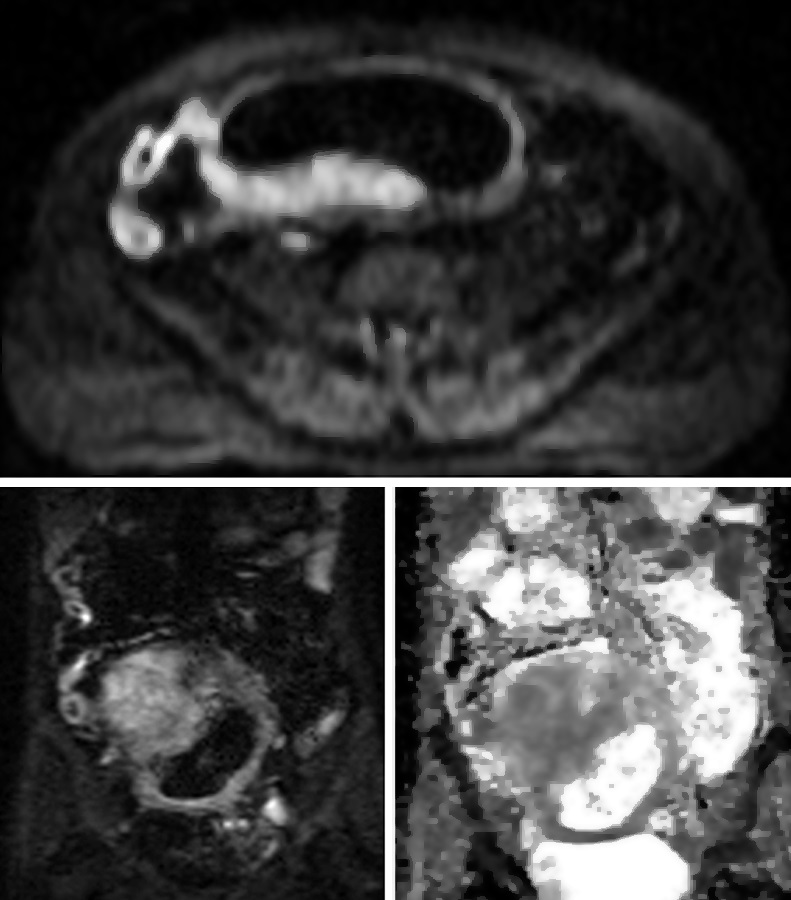

Figura 2

Paciente de sexo masculino de 9 años con antecedente de resección colónica y ostomía por enfermedad de

Crohn. a) Secuencia eco de gradiente coronal donde se idenjpgica el engrosamiento parietal del asa detransitada de

6 mm de espesor (punta de flecha).

b) Misma secuencia muestra adenomegalias ileocólicas de hasta 10 mm como

elemento de actividad (punta de flecha).

c) Secuencia T2 axial con saturación grasa evidencia edema submucoso

como una banda hiperintensa central entre la mucosa y serosa (flecha).